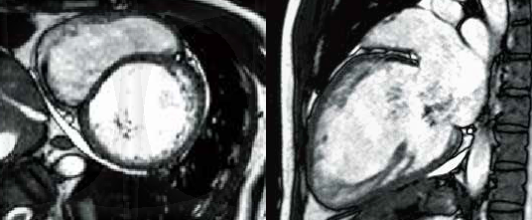

Клінічний випадок 3

Історія пацієнта

Це 44-річний чоловік із застійною серцевою недостатністю та тяжкою МР. Його направили до нашого центру візуалізації для оцінки етіології застійної серцевої недостатності.

Cine MRI in DCM

LV mid-wall enhancement in DCM

Висновки

Кіно МРТ показало помітне розширення ЛШ, серйозне порушення функції ЛШ. На пізньому посиленню гадолінію спостерігалося лінійне посилення в середній стінці міжшлуночкової перегородки. Насичення середньої стінки є типовим паттерном пізнього посилення гадолінію при дилатаційній кардіоміопатії і спостерігається майже у 30% пацієнтів з дилатаційній кардіоміопатії. Це незалежний і потужний інструмент прогнозу при дилатаційній кардіоміопатії поза ФВЛШ.